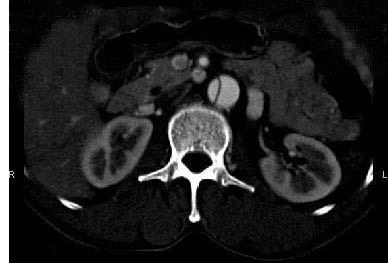

问题 请看一组主动脉的CT增强图像,正确的描述和结论是 ( )

选项 A、真腔较假腔小 B、真假腔之间线状低密度影为内膜片影 C、主动脉瘤 D、主动脉夹层 E、主动脉血栓

答案 ABD